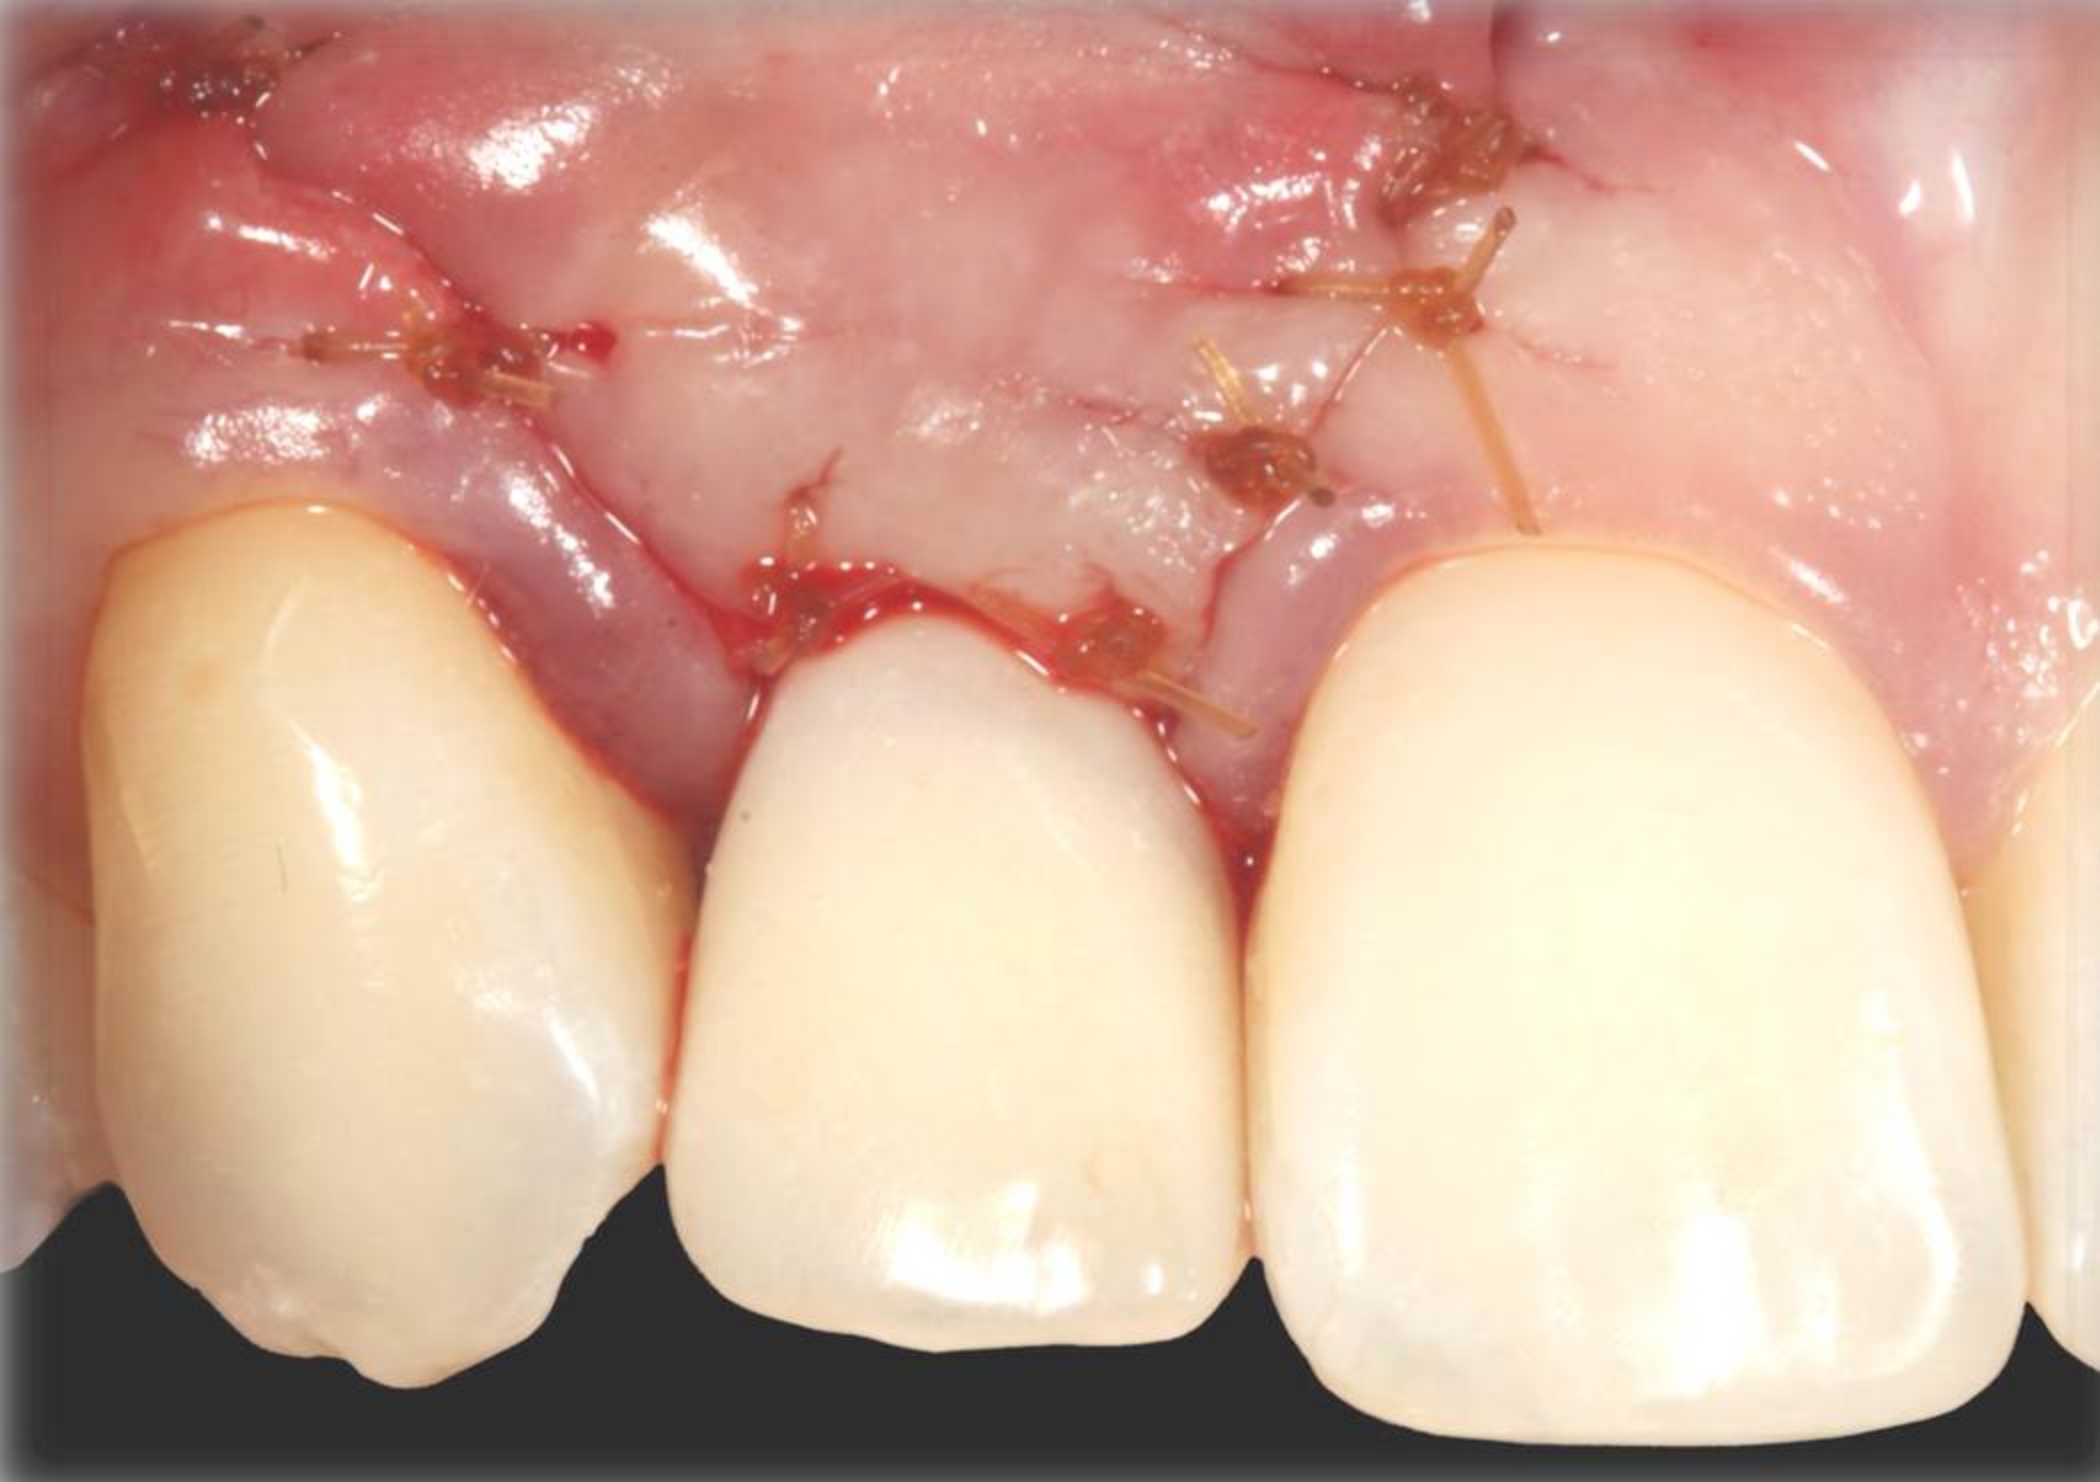

Fig 20. Papillae-sparing incisions were developed both horizontally and vertically. The pedicle flap was elevated, exposing a thin ridge.

Figure 20

Fig 23. The healing abutment in place. Horizontal and vertical incisions were sutured.

Figure 23

There are numerous scenarios when a papilla-sparing incision can be advantageously used, including implant placement, the reconstruction of soft tissue and bone, or both. Figure 10 through Figure 18 and Figure 19 through Figure 25 illustrate how papillae-sparing incisions can be used to restore form and function using a nonsubmerged implant protocol. (Surgeries were performed by DT.)